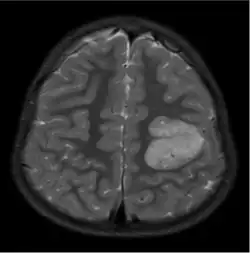

The neurological features of AG tumors are visible via CT scanning or MRI. A clear indication of AG may appear as well-delineated, solid, T2-hyperintense, non-enhancing cortical lesions located in the temporal or frontal lobes in MRI.[1] Another diagnostic trait is a stalk-like extension to adjacent brain ventricles.[13] These traits are similar to low-grade gliomas from a radiological perspective.

The results from CT scanning and MRI are different in terms of clarity and effectiveness of diagnosis. AG displays an expansive non-enhancing cortical tumor in CT scanning, whereas MRI shows a relatively clearer appearance of AG and the tumors appear to be infiltrative, well-defined, and hypointense with T1 lesion.[4] T2/FLAIR lesions indicate AG as a tumor tissue with some extension toward the ventricles along vessels.[4] The possibility of cystic-appearing areas exists as well. In some cases, MRI results show an increase in ribbon-like signal on T1W1 lesions.[4] The clear radiographic outcomes of MRI makes it the more widely used option in the diagnosis of AG.[4]

Nevertheless, precise diagnosis of AG from other phenotypically similar gliomas (such as astroblastoma or ganglioglioma) is a challenge merely based on MRI or CT scanning.[14] The main difference between AG and ganglioglioma could be only AG shows enhancement over time. Compared to AG, astroblastoma often has a discrete border in epithelioid cells and shows vascular sclerosis symptoms.[15]